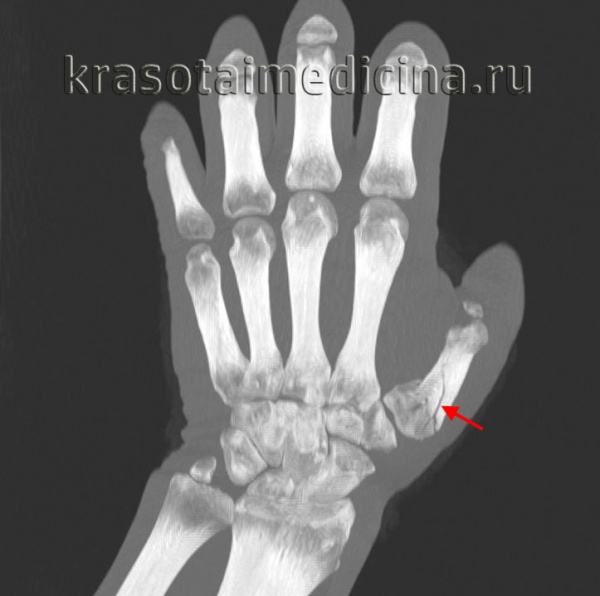

Ротационное смещение можно выявить, сравнивая диаметр костных фрагментов фаланги. Его следует подозревать в случае асимметрии этих фрагментов.

При ротационном смещении линии ногтевых пластинок располагаются непараллельно по сравнению с ногтевыми пластинками пальцев неповрежденной руки